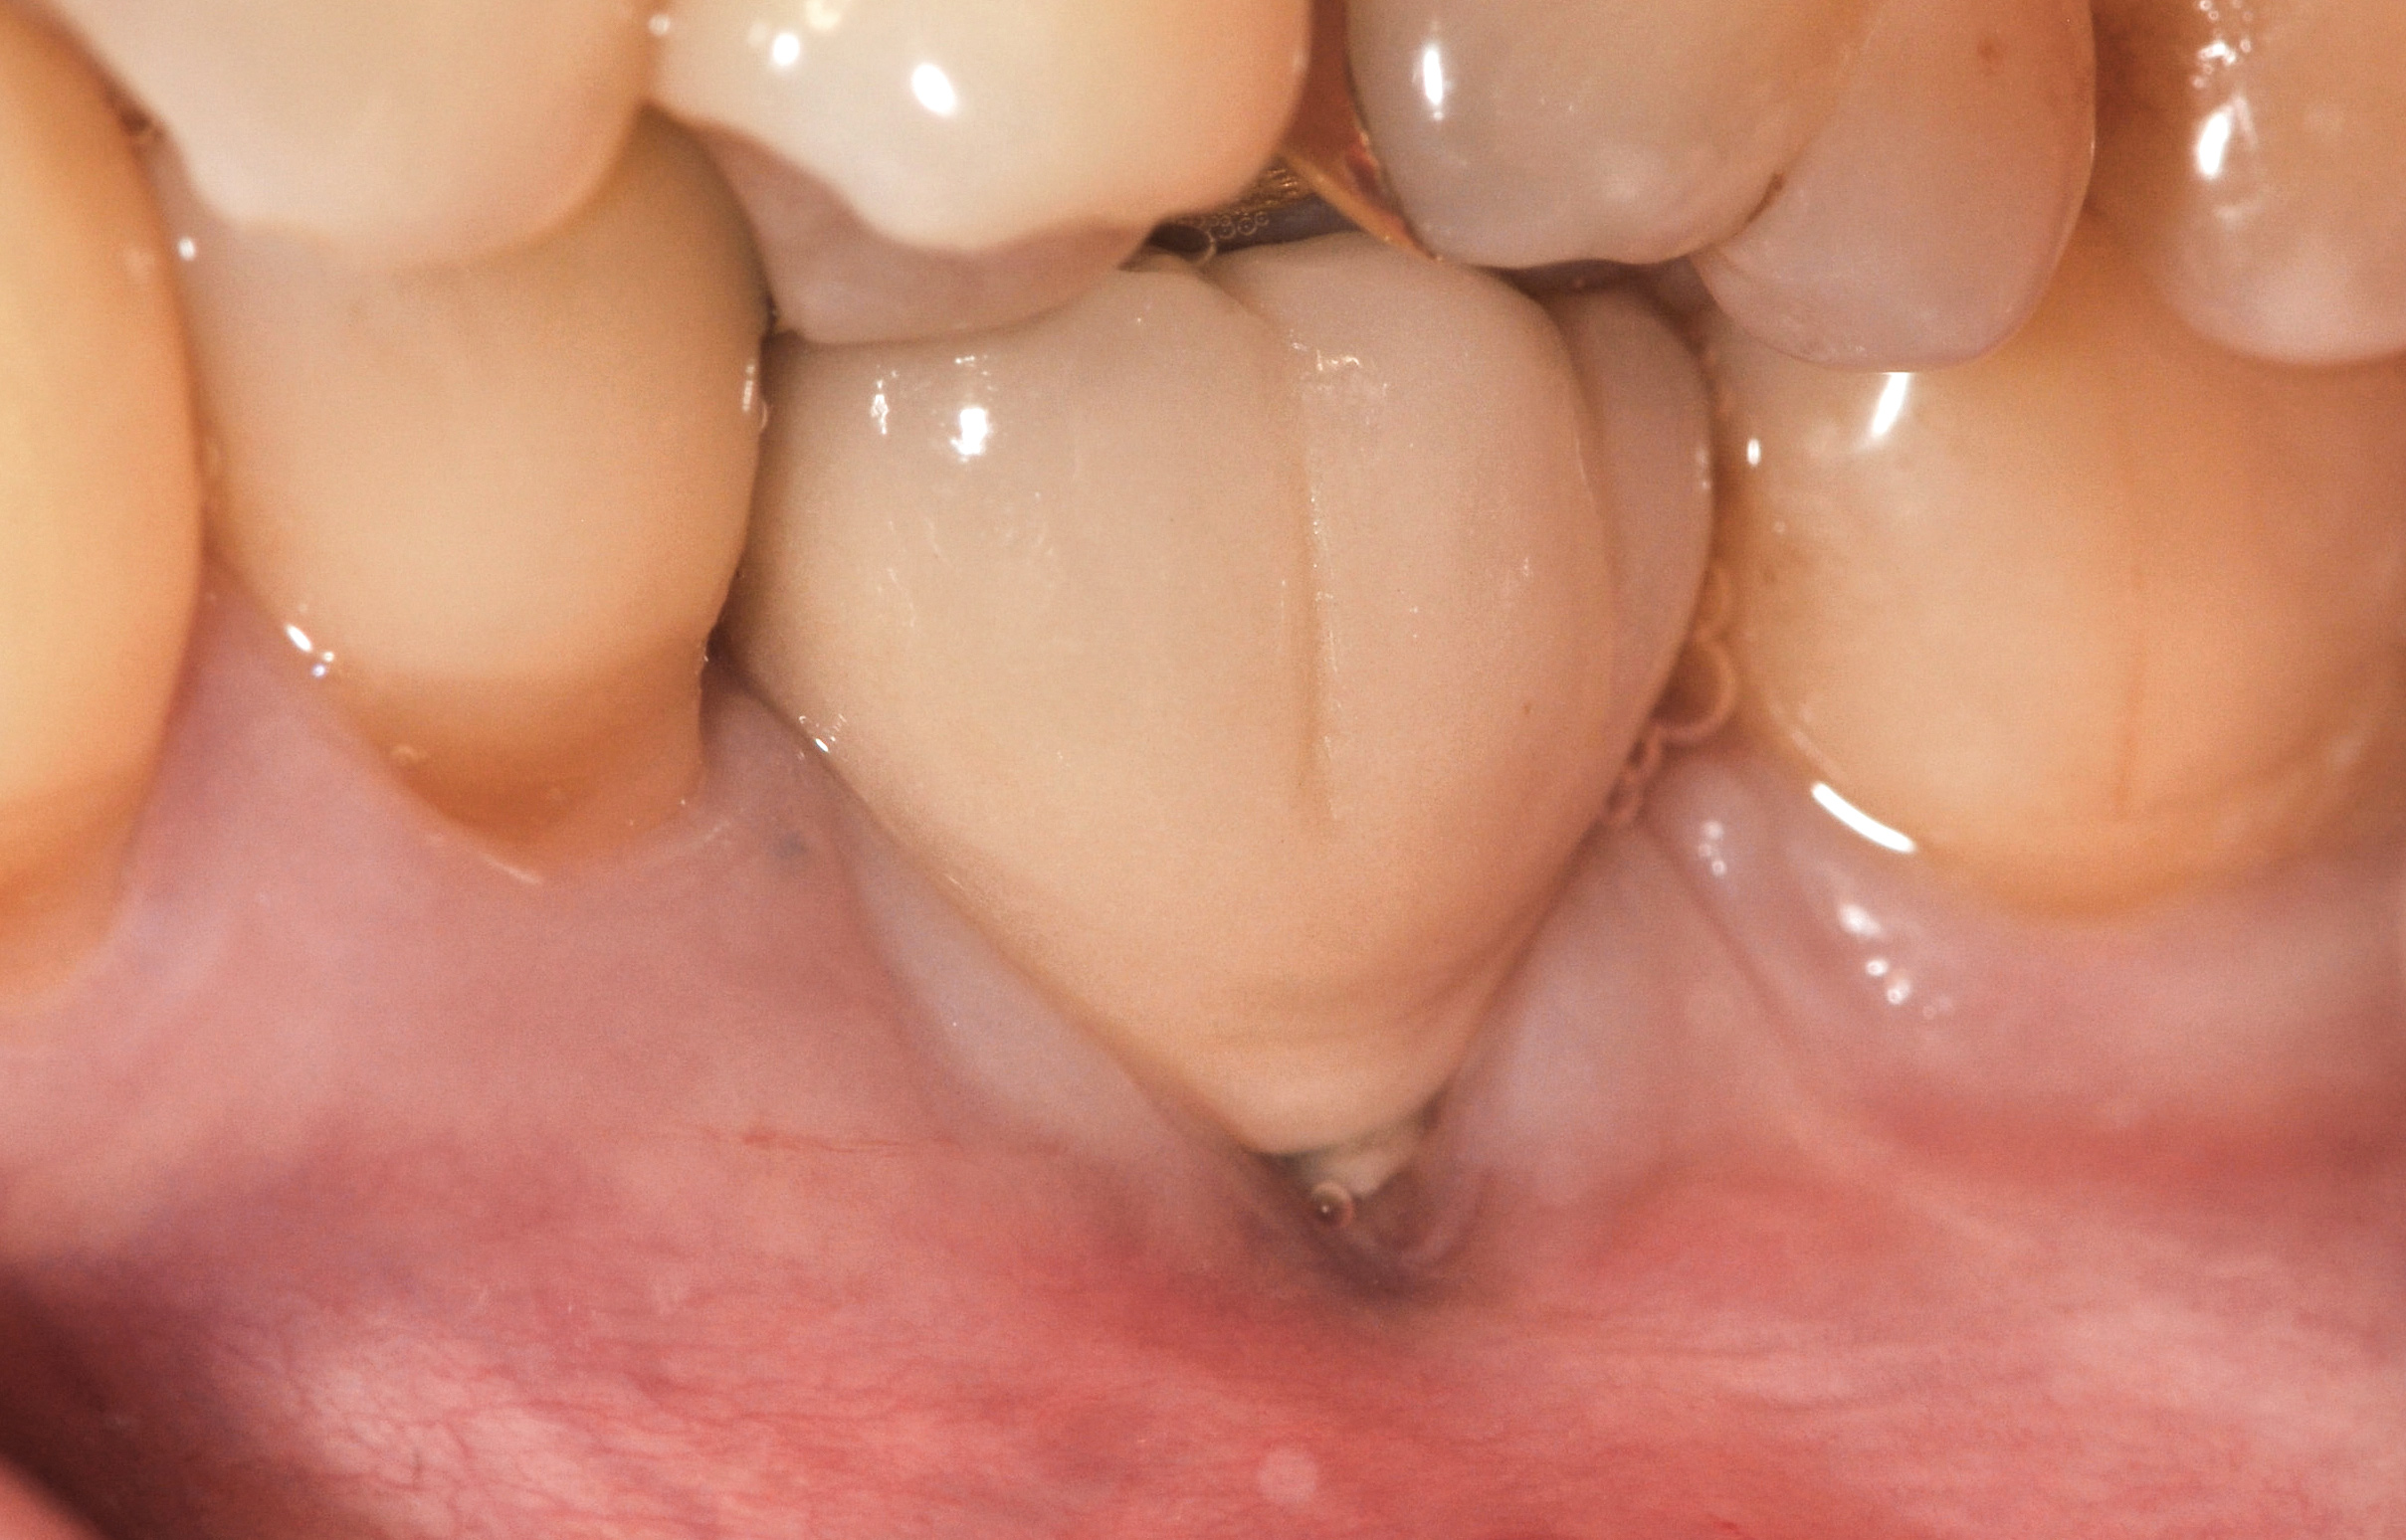

Fig 45. The definitive crown tooth No. 26 seated in place and provisionally cemented. The recession defect was eliminated with the removal and replacement of a new implant in the proper position.

Figure 45

The crown and screw-retained custom abutment were removed, and a surgical cover screw was placed into the implant, thereby allowing spontaneous gingival augmentation in situ (Figure 33 and Figure 34). Note that the lingual aspect of the implant site was significantly more coronal than the labial aspect, which was positive because the defect would be limited to a facial–lingual defect. A fixed RBR bridge was cemented on the adjacent teeth and used as a tooth-supported transitional provisional restoration (Figure 35). A few weeks were allotted to let the soft tissue heal and migrate around the cover screw (Figure 36) to see if there would be complete coverage, thereby allowing a soft-tissue augmentation procedure to be performed with primary flap closure as in clinical scenario No. 2. The major obstacle in achieving a positive tissue response was that the implant depth was also deficient because the implant–abutment connection was at the level of the free gingival margin. It was decided that the best treatment option would be to remove the implant. A high-powered reverse-torque device (Fixture Remover Kit, NeoBiotech, www.neobiotechus.com) was used to remove the implant atraumatically (Figure 38 through Figure 41). The implant socket was allowed to heal for several months not unlike an extracted tooth (Figure 42). A new implant was placed in a better position from both a restorative and esthetic perspective (Figure 43), and after a few months of healing, a new crown was made (Figure 44). A satisfactory functional and esthetic result was achieved (Figure 45 and Figure 46) without employing pink porcelain.